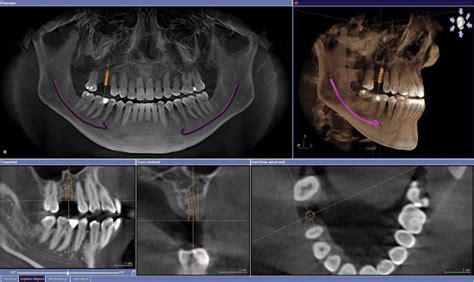

El Tac dental, también conocido como Tomografía Computarizada de Haz Cónico (CBCT, por sus siglas en inglés), es una técnica avanzada de imagen que proporciona una visión tridimensional detallada de la estructura oral y maxilofacial. A diferencia de las radiografías convencionales, el Tac dental ofrece una representación más precisa y completa de los tejidos, huesos y dientes en la boca.

El proceso de obtención de un Tac dental implica el uso de una máquina de rayos X especializada que toma múltiples imágenes en forma de cono alrededor de la cabeza del paciente. Estas imágenes se combinan mediante un software avanzado para generar una reconstrucción tridimensional de alta resolución. Esto permite a los profesionales de la odontología obtener una visión detallada de la mandíbula, el maxilar, los dientes, los nervios y otros tejidos circundantes.

El Tac dental proporciona una visión tridimensional precisa y detallada de los tejidos orales y maxilofaciales. Esto permite a los dentistas evaluar la densidad ósea, identificar estructuras anatómicas importantes y planificar con precisión la colocación de los implantes dentales.

Con la información proporcionada por el Tac dental, los dentistas pueden planificar con precisión la posición y el ángulo de los implantes dentales. Esto les permite determinar el tamaño y el tipo de implante adecuados para cada paciente, lo que resulta en una colocación más precisa y una mayor tasa de éxito a largo plazo.